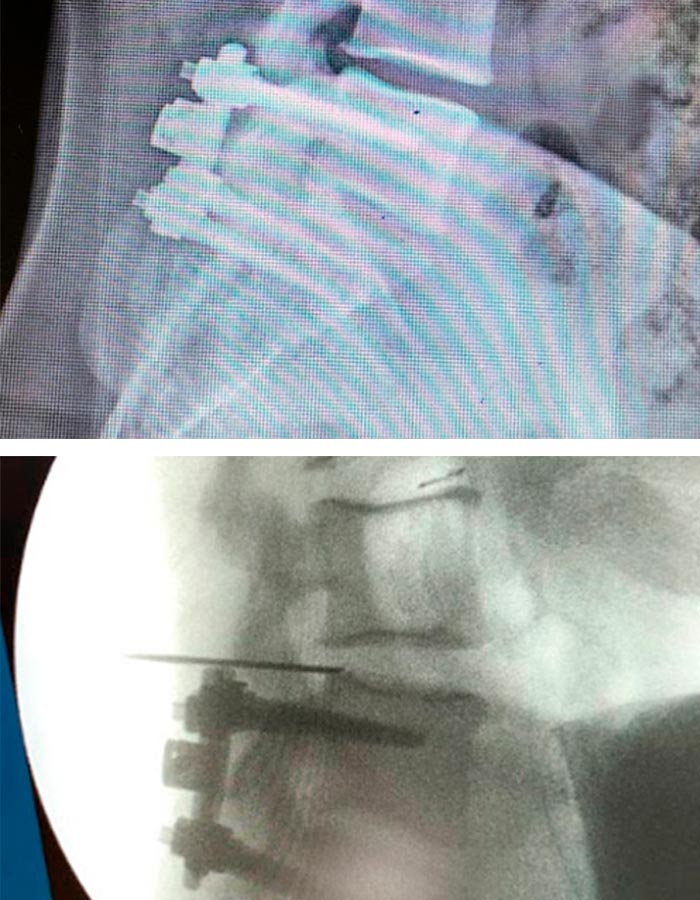

Operación

La cirugía mínimamente invasiva de endoscopia de avanzada de columna se lleva a cabo en unas dos horas a través de un portal de unos 3mm, situado en la parte posterior de la columna :

1. Se introduce una aguja guía que nos ayudará a introducir un dilatador para acceder a la zona de trabajo sin dañar ningún tipo de tejido.

Tras una cirugía que transcurre sin incidencias ni complicaciones, el postoperatorio está marcado por una mejora considerable del dolor lumbar del paciente y una liberadora sensación en las piernas y una desaparición del dolor sufrido por la Hernia de 2cm que se le extrae.

Un nuevo caso de éxito para el Instituto de Columna Vertebral.